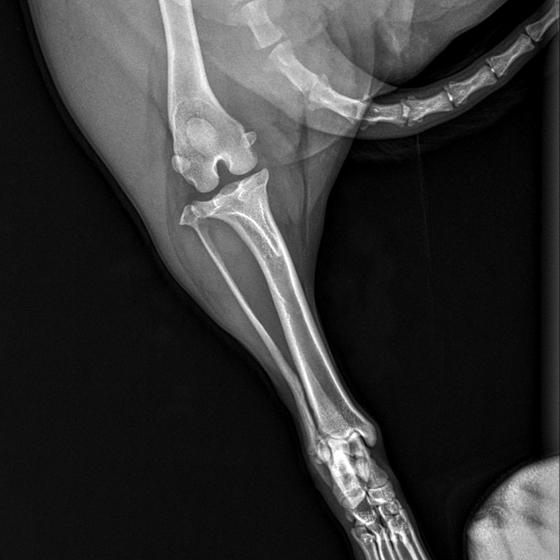

Karola nám doviezla pani, ktorá ho našla, asi jediná dobrá duša, ktorá pri ňom neprešla so zatvorenými očami. Ihneď sme s krpcom utekali na veterinu aby sa zistila závažnosť jeho zranení. Hneď pri prvých RTG snímkoch sa ukázala obojstranná fraktúra panvy, taktiež fraktúra krídla panvy a keby mu to chudákovi nestačilo, do tretice sa objavila zlomenina stavca. Karolko mal neznesiteľné bolesti, ale krásne prečkal vyšetrenie lebo vedel, že je v dobrých rukách a dostáva sa mu pomoci. Po nálezoch sme okamžite kontaktovali neurológiu a ortopédiu na veterinárnej klinike Sibra - centrum veterinárnej medicíny, kde sme dostali hneď termín na príjem.

S obrovskou radosťou sme počúvali slová neurológa, MVDr. Hájeka keď nám oznámil, že...

Karol nemá žiadne neurologické deficity, po ortopedickej operácii bude vedieť behať a bez problémov bude vedieť samostatne cikať a kakať. Po tejto úžasnej správe sme samozrejme dali zelenú náročnej ortopedickej operácii pod vedením MVDr. Vatolíka. Operácia sa podarila na výbornú, Karči je "zoskrutkovaný" a vôbec nič mu nebráni v tom, aby opäť mohol behať a aktívne žiť. Momentálne sa zotavuje po operácii, musí mať prísny kľudový režim. Po vybratí stehov ho čaká hydro- a fyzioterapia, ktorá mu pomôže postaviť sa na nohy. Je to bojovník, veľmi sa chce uzdraviť a v jeho očkách je dokonale vidieť, že už kuje plány čo všetko zameškané bude musieť dobehnúť.